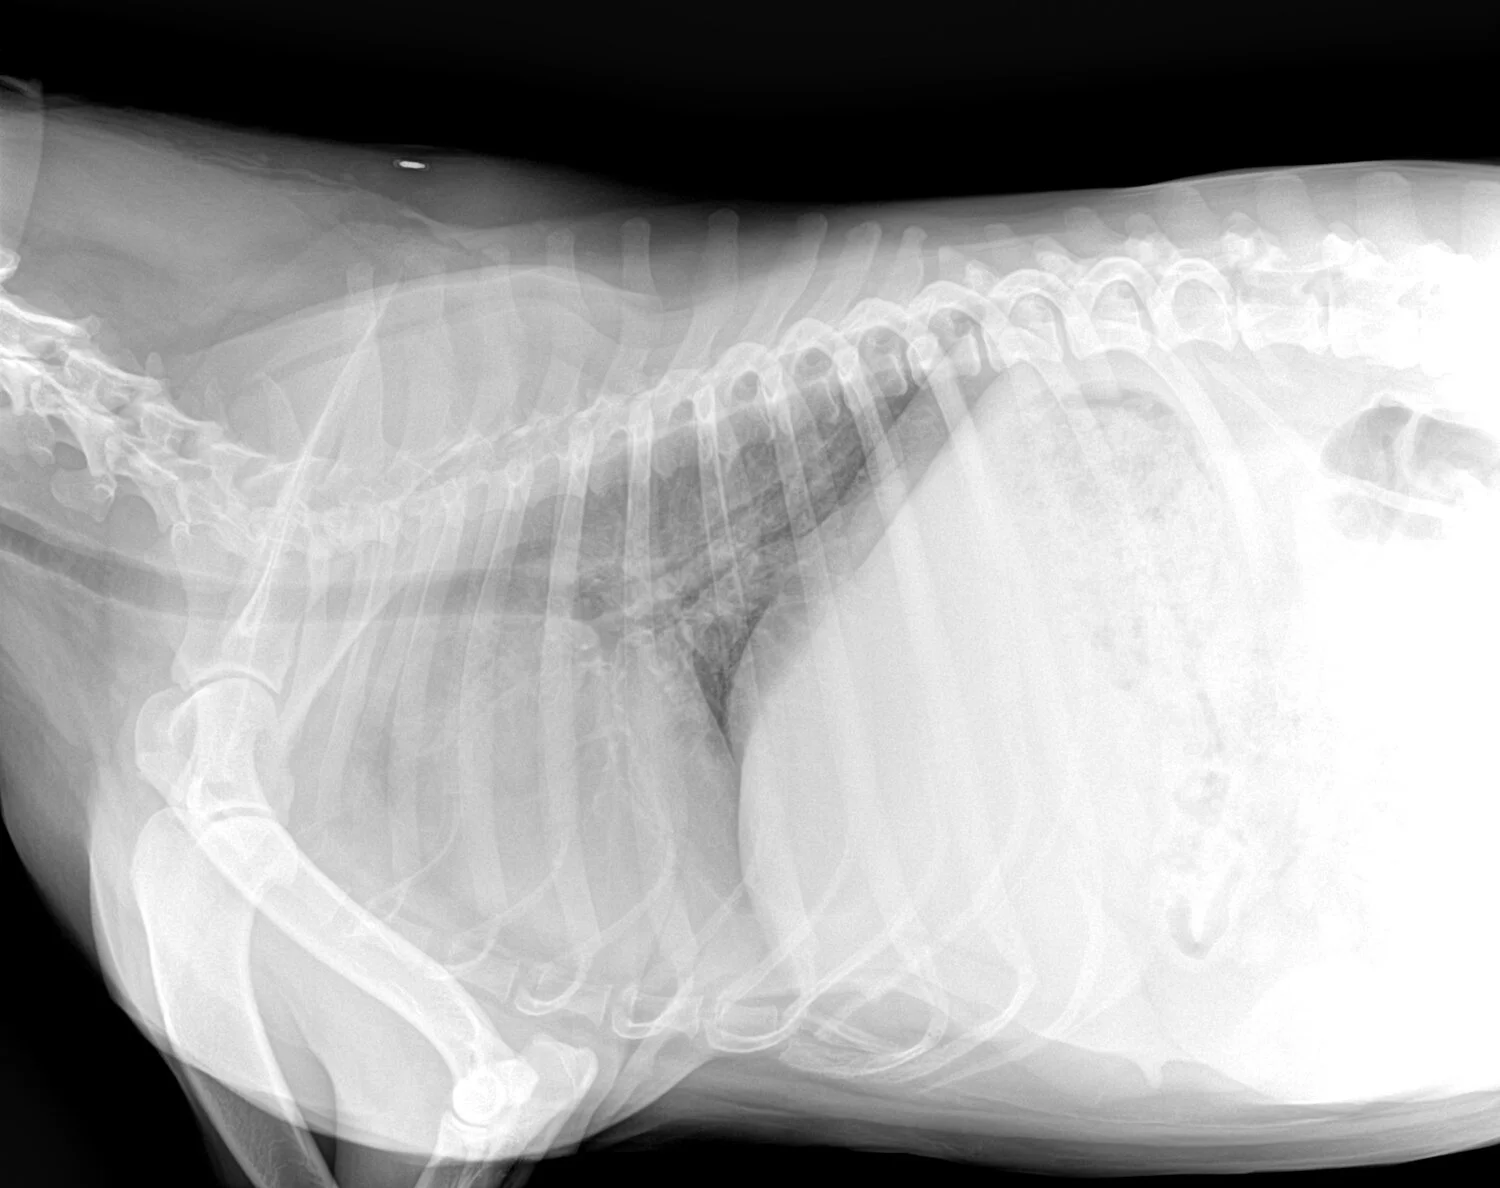

Identify the type of radiograph taken?

R lat thorax